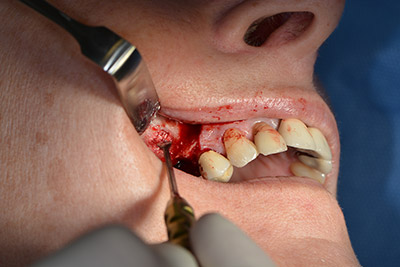

Dunque, l'impianto viene posizionato e l'osso ricostruito. In questo caso, considerate le dimensioni della regione di accrescimento, i microframmenti dell'osso autologo (raccolti con un'apposita cannula di aspirazione in seguito alla perforazione dell'impianto 16 e della fenestrazione 14) vengono combinati con dei materiali di riempimento dell'osso.

Una membrana riassorbibile viene usata come barriera in direzione buccale per contenere l'accrescimento. Infine, vengono applicate suture resistenti alla saliva (da fig. 15 a 19).